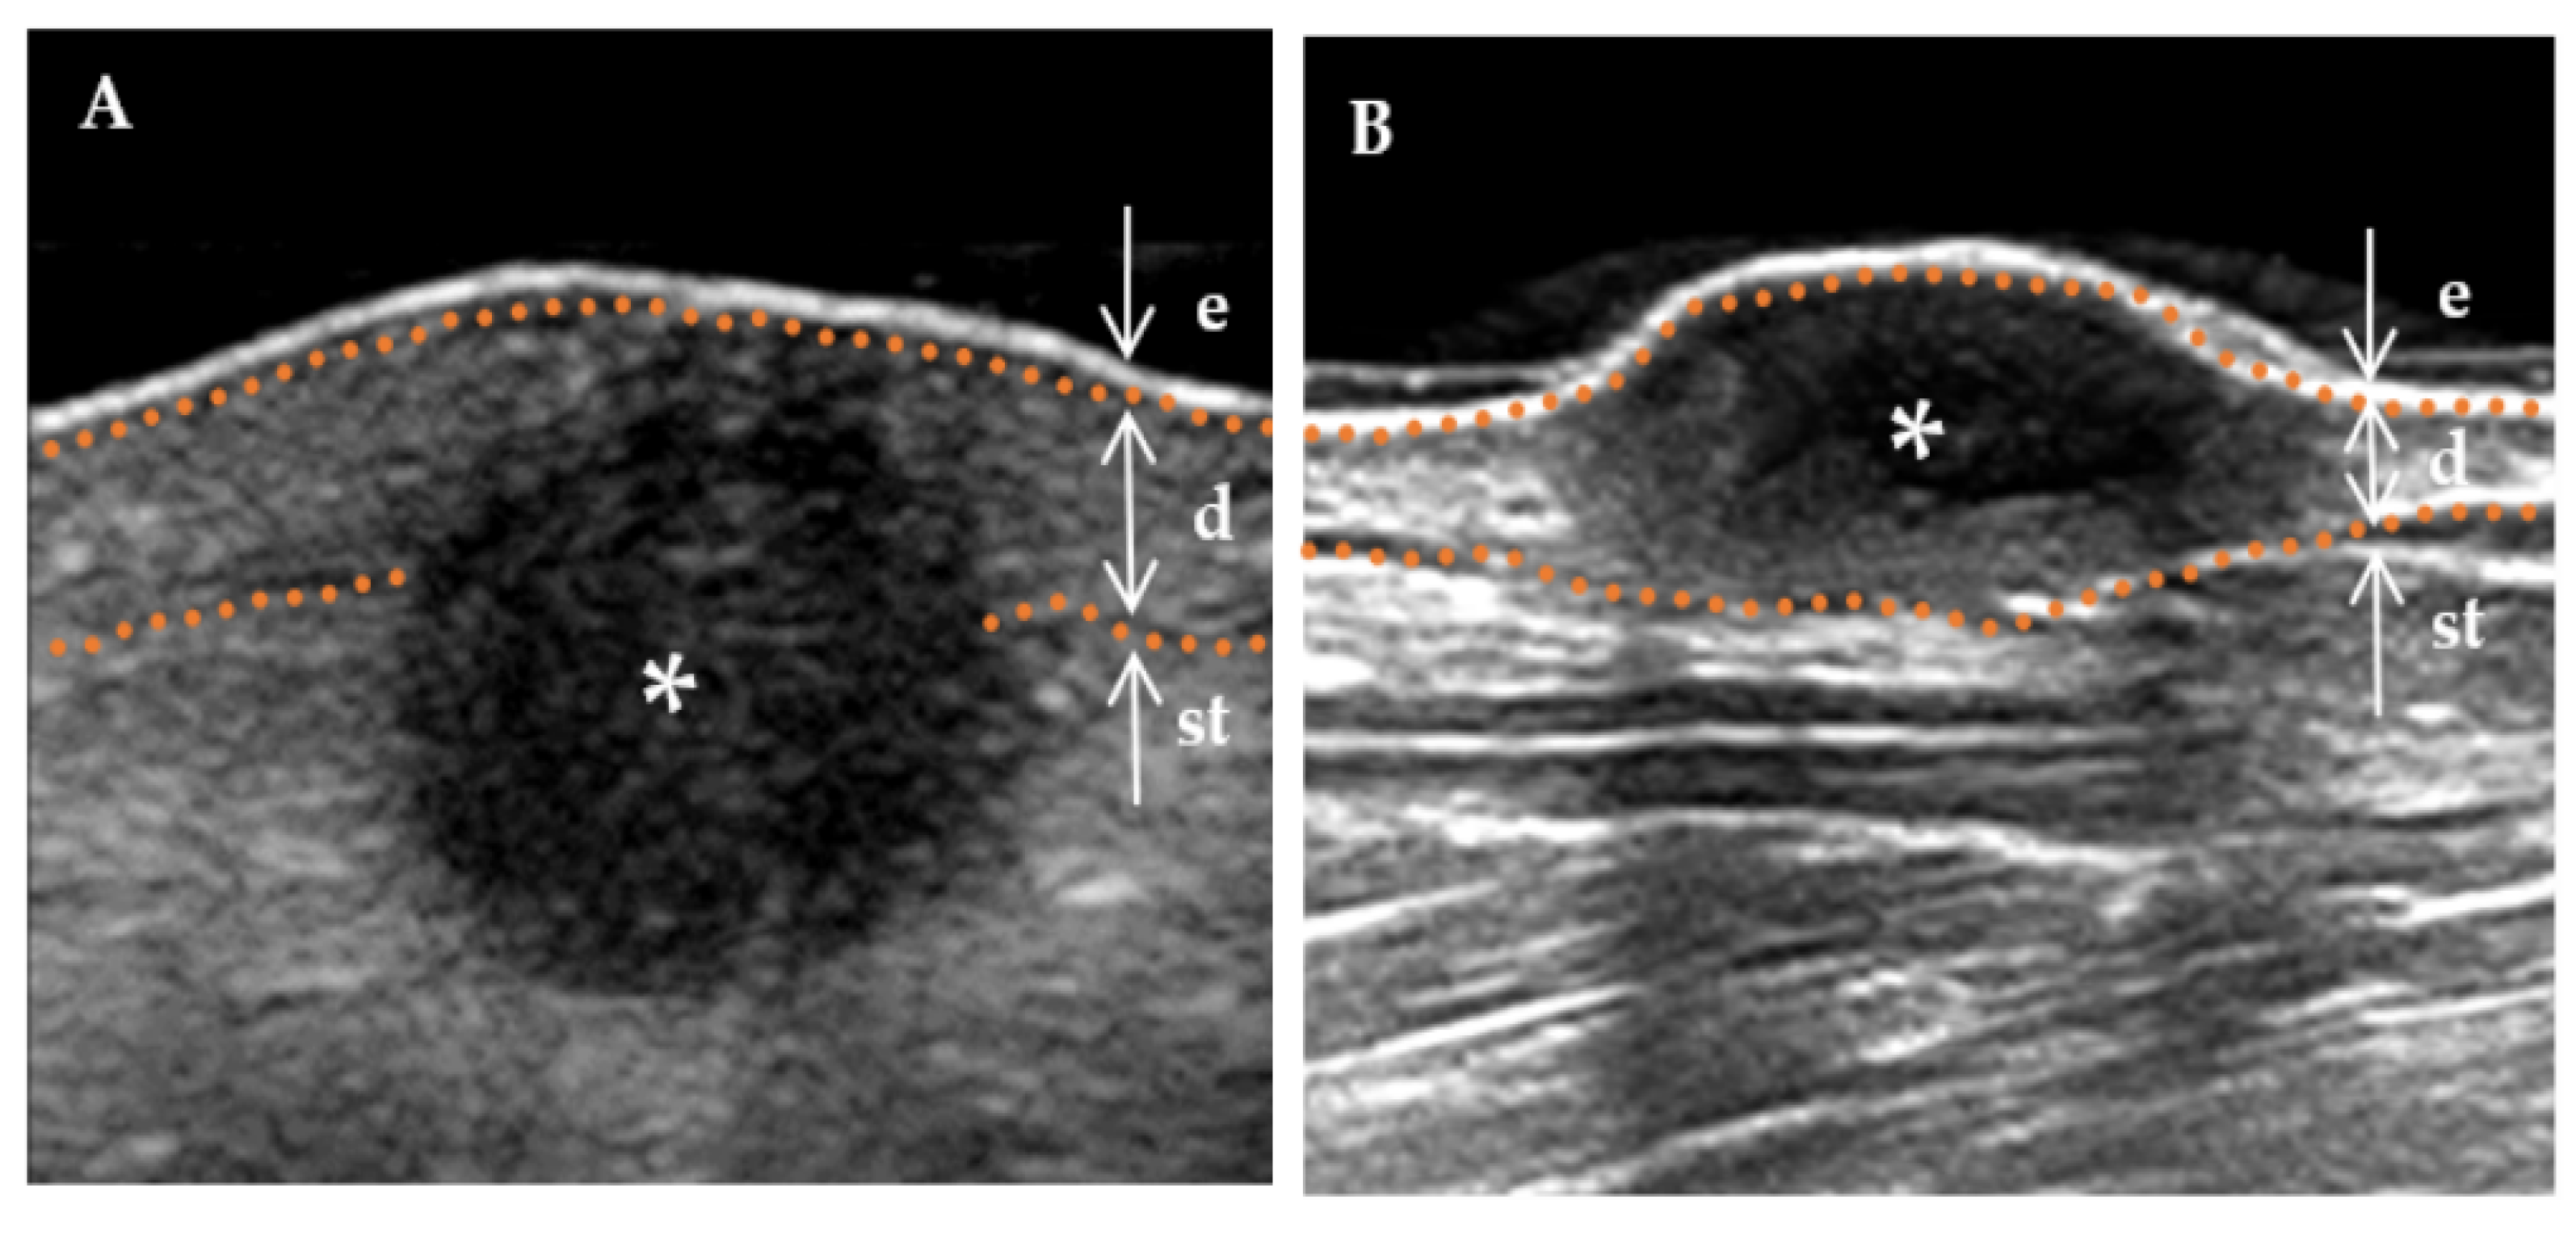

| shape, n (%) | 0.001 * | ||

| Regular (incl. creeping) | 5 (29.4%) | 26 (78.8%) | |

| Irregularity | 12 (70.6%) | 7 (21.2%) | |

| Morphology of surface, n (%) | 0.335 | ||

| Concave | 0 (0.00%) | 2 (6.1%) | |

| Flat | 7 (41.2%) | 16 (48.5%) | |

| Protuberance | 10 (58.8%) | 15 (45.4%) | |

| Internal echogenicity, n (%) | 0.004 * | ||

| Homogenous | 4 (23.5%) | 27 (81.8%) | |

| Heterogenous | 13 (76.5%) | 6 (21.2%) | |

| Stratum basal, n (%) | 0.002 * | ||

| Dermis | 6 (35.3%) | 26 (78.8%) | |

| Subcutaneous | 11 (64.7%) | 7 (21.2%) | |